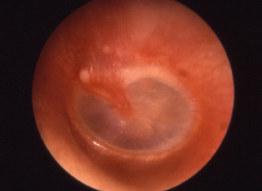

• Тимпанометрія або акустичної імпедансометрією – є ультразвуковим обстеженням середнього вуха, переважно слухової труби. Метоютимпанометріїєоцін-

ка стану пошкодження чи цілісності барабанної перетинки та слухових кісточок.

В основу методу покладено

використання звукового тиску з певною частотою та інтенсивністю у вусі.